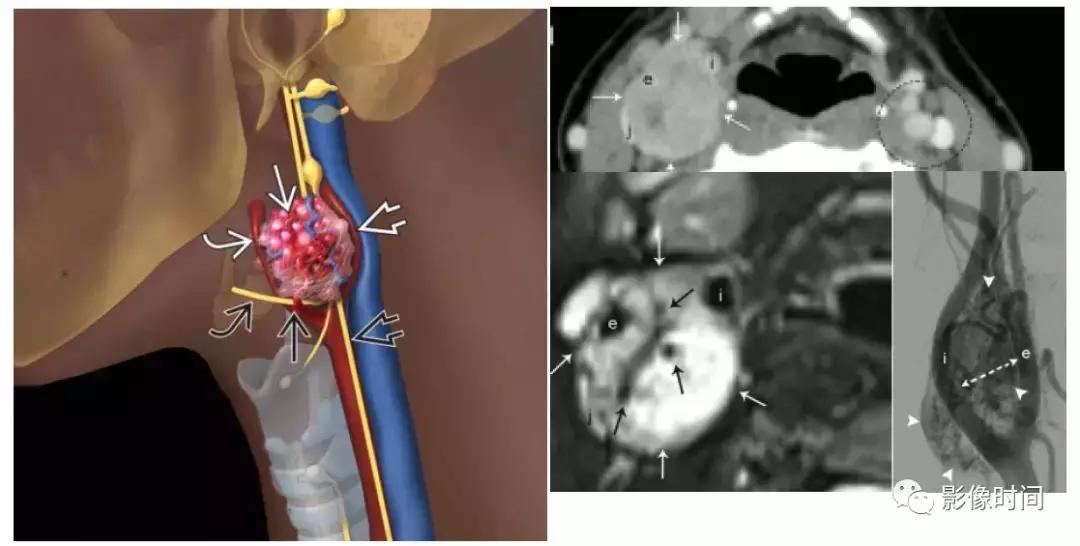

(1).颈动脉体瘤:约占颈部副节瘤的 60%,45-60 岁多见,无明显性别差异。多位于颈总动脉分叉处内侧,往往生长缓慢和无痛,由于病灶靠近 10-12 颅神经,因此患者可以出现吞咽困难、声音嘶哑等。

模式图显示颈动脉体瘤富含血管,并导致颈内动脉及颈外动脉距离增宽,包绕颅神经。增强 CT 显示右侧动脉间隙中心的边界清晰肿块,导致颈内动脉 (i) 和颈外动脉 (e) 分离。颈内静脉向外后移位(j)。左颈动脉间隙 (虚线圆) 显示颈动脉与颈内静脉的正常关系。T2WI 显示边界清晰的信号肿块 (白色箭头),多个内部流动信号 (黑色箭头)。DSA 显示颈动脉分叉处有富血管团块 (箭头)。

(2).颈静脉球瘤:可发生于舌咽神经鼓室支或迷走神经耳支,50-60 岁男性多见,临床症状多为耳鸣、听力损失或眩晕,和其他与颈静脉孔内的颅神经有关的症状。

模式图显示颈静脉球瘤富含血管,包绕颅神经伴「虫噬状骨质破坏」。CT 显示颈静脉孔区「蛀虫」的骨质破坏。增强 MRI 显示颈静脉孔区增强肿块 (白色箭头),注意流空信号 (黑色箭头)。

(3).迷走神经球瘤:约占颈部副节瘤的 2.5%,40-60 岁女性稍多见,最常发生迷走神经节(约平 C1)。临床表现为下颌角后方无症状肿块,后期可能出现迷走神经功能障碍如吞咽困难、声带麻痹等症状。迷走神经位于颈动脉间隙的后侧,因此,迷走神经球瘤向前推挤颈内或颈外动脉。

模式图显示迷走神经球瘤位于约颈 1 水平,富含血管,颈内动脉受压向前内移位。T2WI 显示一个边界清晰高信号肿块 (白色箭头) 与流空血管 (黑色箭头)。注意右颈内动脉 (i) 和颈外动脉 (e) 的前移位,右颈内静脉外移位(j)。DSA 显示颈动脉分叉处上方高血管团块 (白箭头)。